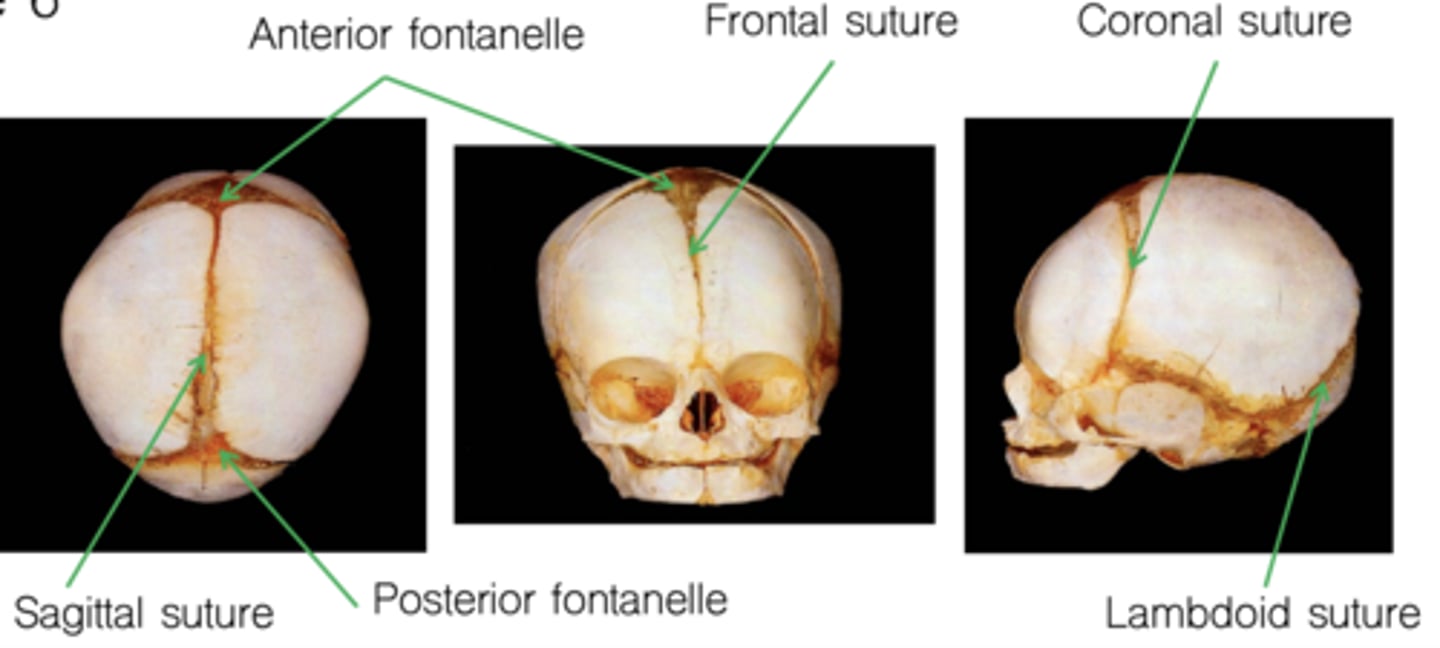

Infant Skull: Pre-sutures

"Soft spots" in infant skulls

Close at various times

- Posterior fontanelle (sagittal & lambdoid suture): by 6 months

- Anterior fontanelle (frontal & coronal sutures): ~middle of second year

Craniosynostosis

Premature fusing of sutures